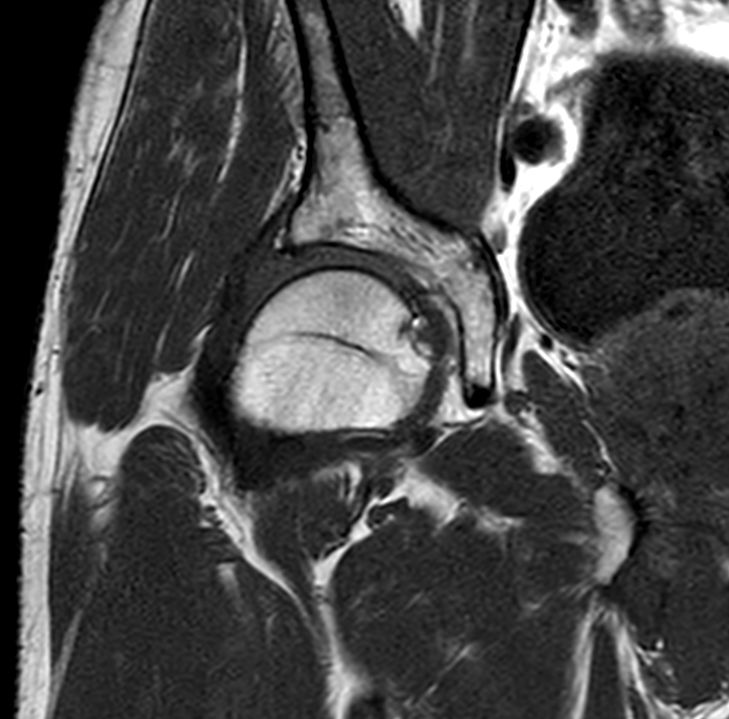

Sagittal T2w TSE

Sagittal T2w TSESmartSpeed

Sagittal T2w TSESmartSpeed Resolution